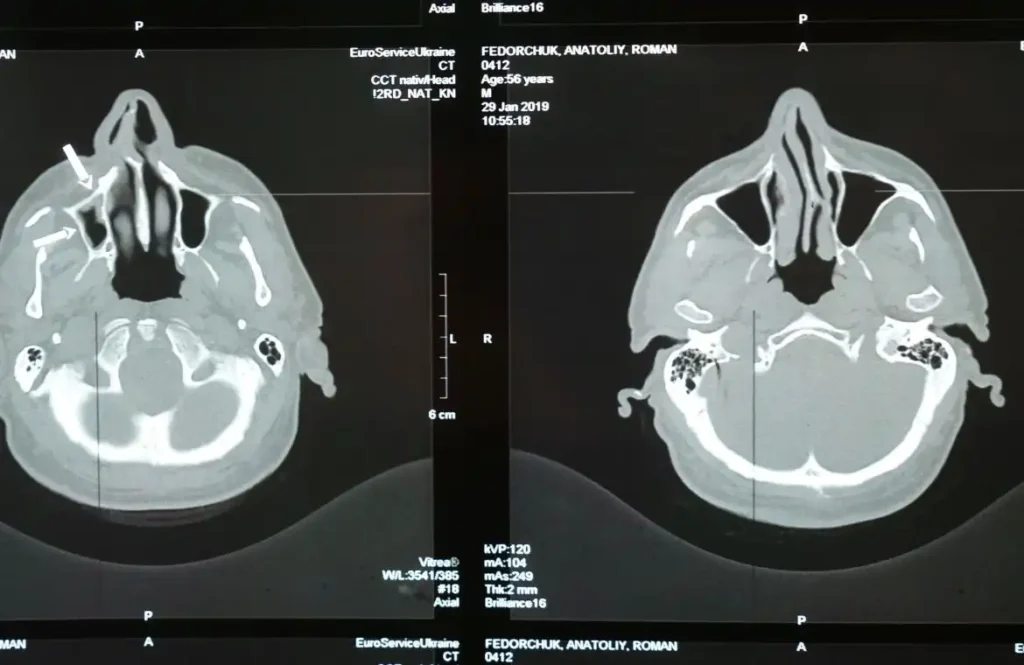

Un estudio reciente publicado en una revista de neurología ha encontrado una correlación entre la enfermedad periodontal y el daño en la sustancia blanca del cerebro. La sustancia blanca es crucial para la comunicación entre diferentes áreas del cerebro, y su deterioro puede resultar en problemas de memoria, dificultades cognitivas y un mayor riesgo de accidentes cerebrovasculares. Este hallazgo sugiere que la salud bucal podría desempeñar un papel importante en la salud cerebral, un área que aún se está explorando.

El estudio analizó a 1,143 adultos con una edad media de 77 años. Se realizó una revisión dental para determinar la presencia de enfermedad periodontal, y se llevaron a cabo escáneres cerebrales para identificar signos de daño en los vasos sanguíneos del cerebro. Los resultados mostraron que el 28 % de los participantes con enfermedad periodontal presentaban un mayor volumen de hiperintensidades en la sustancia blanca, en comparación con el 19 % de aquellos sin problemas dentales.

Además, se encontró que las personas con enfermedad de las encías tenían un 56 % más de probabilidades de estar en el grupo con mayor volumen de hiperintensidades. Aunque el estudio no establece una relación causal directa, sí sugiere que la inflamación oral podría estar relacionada con el deterioro cerebral. El Dr. Souvik Sen, autor principal del estudio, enfatiza que estos resultados refuerzan la idea de que una buena salud bucal puede contribuir a mantener un cerebro más sano.